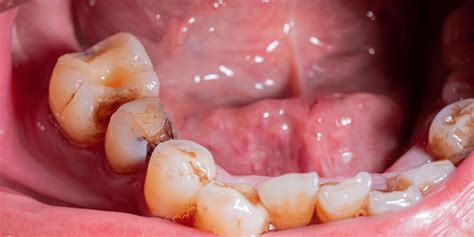

Las caries afectan actualmente al 21% de la población (según datos del Instituto Nacional de Estadística), siendo una de las patologías dentales más comunes. Un tipo de caries que suele afectar a muchos pacientes son las caries interdentales o interproximales. Estas caries son el tipo más difícil de diagnosticar ya que, con frecuencia, no se puede detectar visual o manualmente con un explorador dental. Por el lugar donde se originan, las caries interproximales pueden ser menos visibles y difíciles de detectar. Las caries interproximales o interdentales son el enemigo invisible que toda boca saludable no quiere tener, ya que son las más difíciles de detectar a simple vista, y generalmente se pueden observar mediante el uso de rayos X.

Una caries es una zona dañada del diente, donde la acumulación de placa bacteriana ha provocado una erosión permanente y deberá tratarse para frenar su expansión. La caries dental es una enfermedad en la que los procesos bacterianos dañan la estructura dura del diente formada por el esmalte, la dentina y el cemento. Inicialmente, pueden aparecer como una pequeña área descalcificada que puede convertirse en una gran cavitación.

La zona que está entre los dientes es más inaccesible y durante el cepillado dental será más difícil de limpiar. Por lo tanto es una zona propensa a la acumulación de placa bacteriana y sarro que provoca las caries. Por otro lado, el esmalte que recubre el diente desde arriba hasta la dentina es suficientemente denso, lamentablemente no es así en los laterales, pues allí la capa de esmalte es de menor consistencia, por lo que la caries puede penetrar con más facilidad hasta el nervio.

Como ya hemos mencionado anteriormente, las caries interproximales suelen ser complicadas de detectar a simple vista y por eso es necesario acudir al odontólogo para que nos las diagnostique a tiempo. Muchos pacientes se dan cuenta de que tienen una caries interproximal cuando ya sienten síntomas de dolor y sensibilidad dental, momento en que la caries ya ha erosionado parte de la estructura dental.

¿Qué aspecto tiene una caries en una radiografía?

La desmineralización y destrucción de las capas del diente se observa como una imagen radiolúcida (zona negra alrededor/dentro del diente). En la consulta dental realizamos controles radiográficos periódicos. Se hacen cada 6, 9 o 12 meses, dependiendo del riesgo de caries del paciente, la presencia de múltiples reconstrucciones interproximales (interdentales), etc.

En la imagen de la izquierda se aprecia una caries debajo de un empaste antiguo.

Es importante tener en cuenta que el diagnóstico temprano de las caries repercutirá en un mejor pronóstico del diente. En obturaciones antiguas (empastes/reconstrucciones) controlaremos que los márgenes de las restauraciones estén correctos, ya que en el material artificial no se producirán caries, pero en el tejido dental de alrededor sí podrían aparecer filtraciones. En la imagen que señala la flecha vemos una imagen radiolúcida (oscura) que indica la falta de material dental, la presencia de una zona “hueca”. Caries.